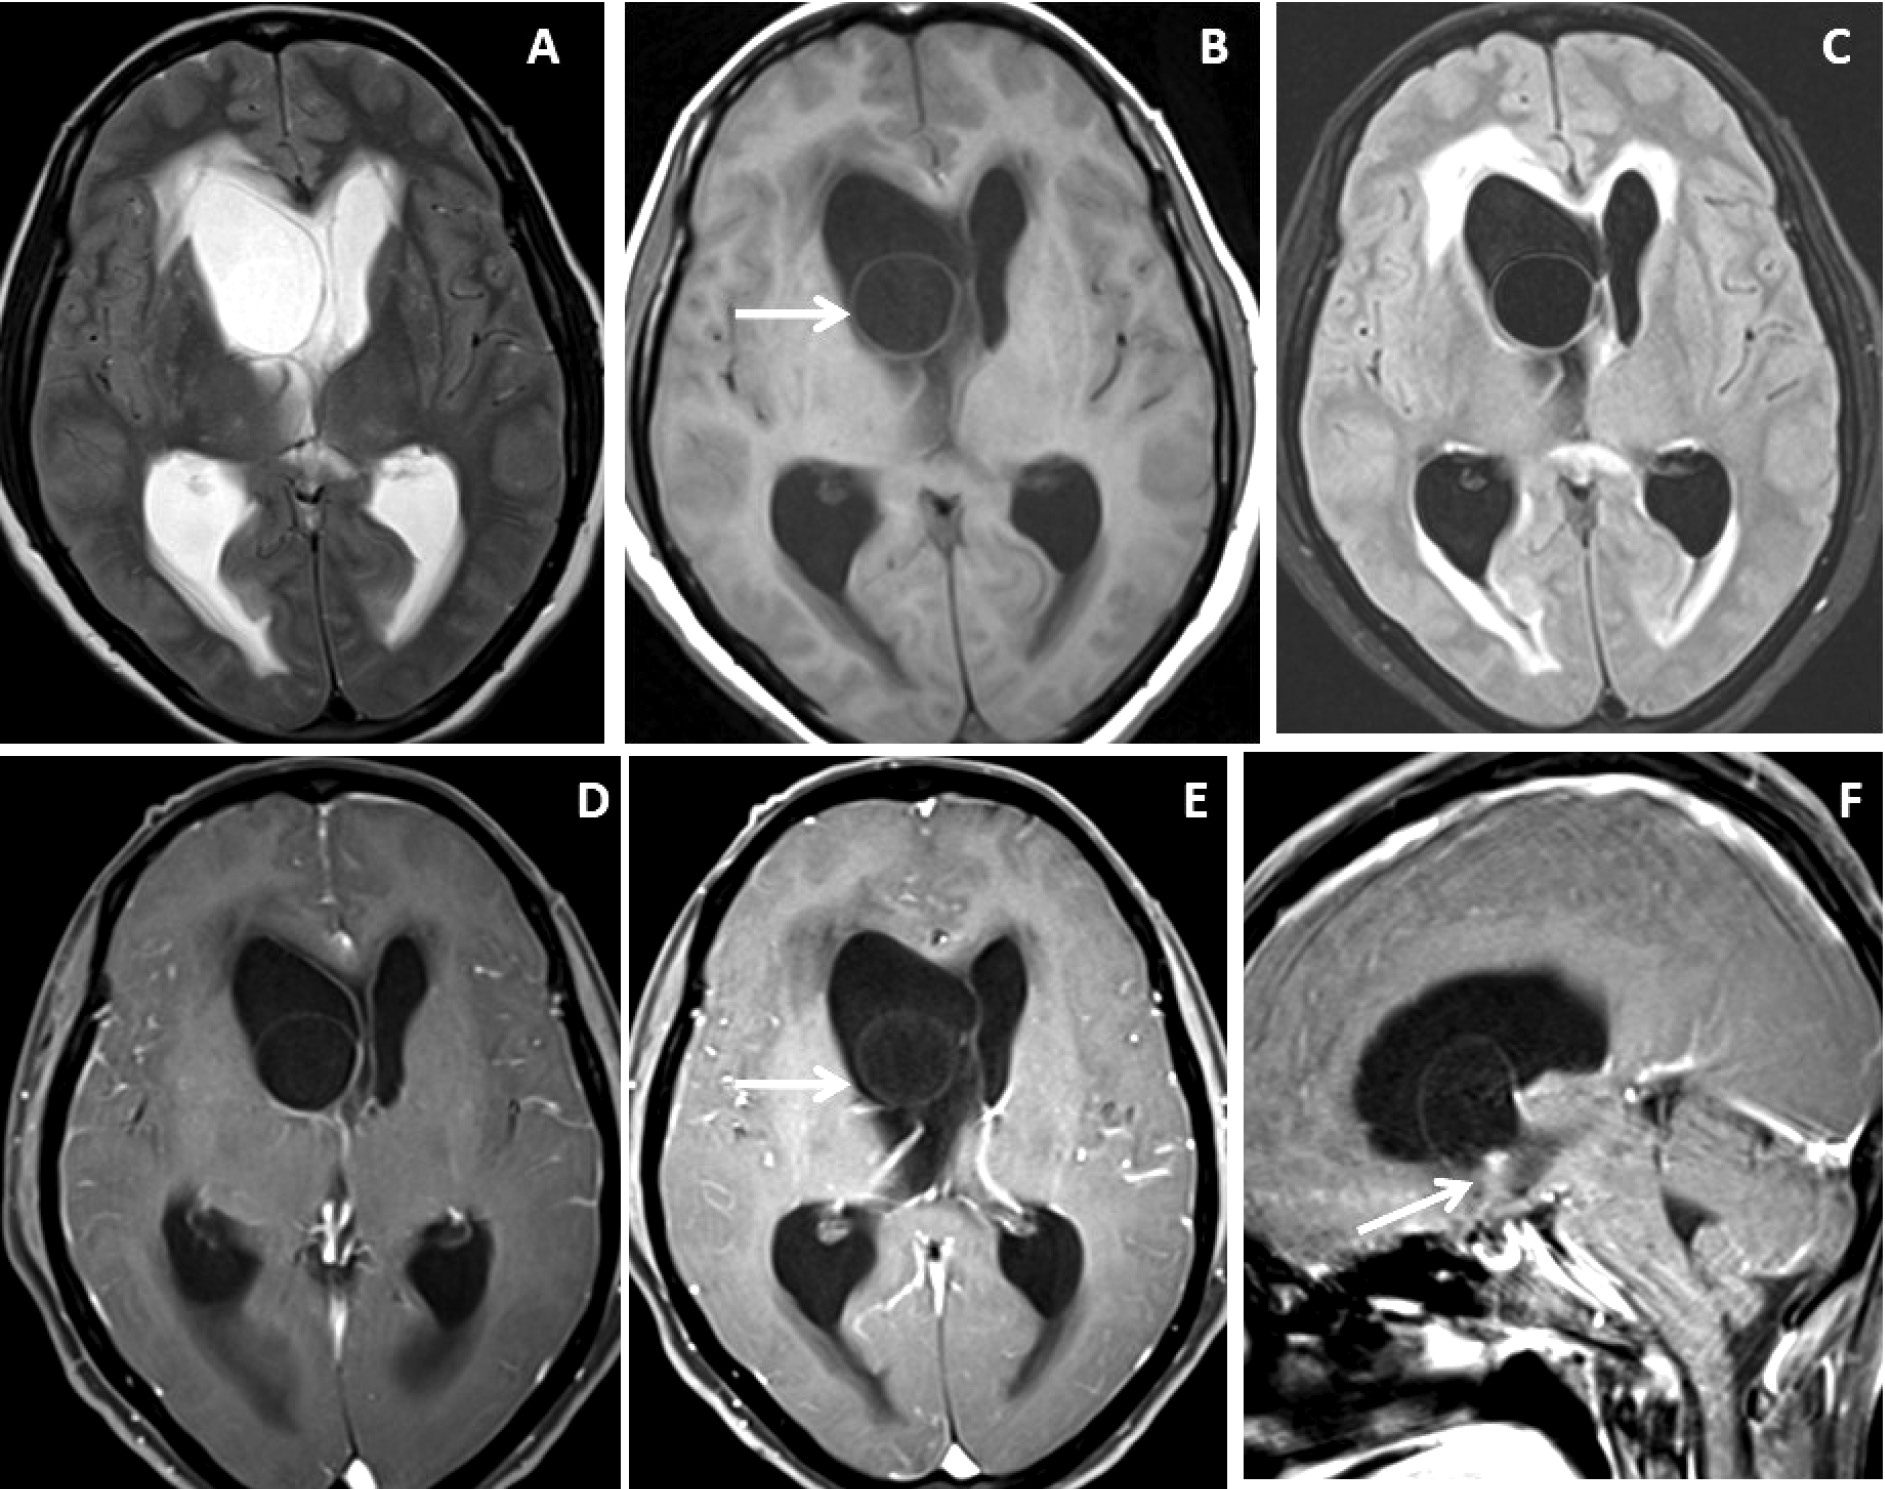

Figure 2. Brain magnetic resonance imaging of 50 years female with acute severe headache with acute neurological status and semi-comatose state. (A-C) Axial T2WI, FLAIR and T1WI images show a thin-walled T2 hyperintense cystic lesion in the frontal horn of the right lateral ventricle occluding the right-sided foramen of Monroe(arrow) with marked supratentorial hydrocephalus with periventricular CSF seepage. (D-F) Axial and sagittal post-gadolinium T1W images show smooth peripheral cyst wall enhancement (arrow) with a small enhancing mural nodule inferiorly (arrow in image F).

T2WI, DRIVE and SWI visibility score of the wall of intraventricular neurocysticercosis: Of 10patients with IVNCC, the cyst wall was distinctly visualized (visibility score 2) in 1 (10%) patient on T2WI, 8 (80%) patientson 3D-DRIVE (Figure 1 and 2) and 6 (60%) patients on SWI sequence. For identification of wall of IVNCC with a visibility score of 2, the 3D-DRIVE sequence had a sensitivity of 80% followed by 60% with SWI and 10% with T2W images. Cyst wall calcification was identified in 1(10%) patient on SWI. Poorly visualized wall of intraventricular neurocysticercosis (visibility score 1) noted in 2(20%) patients on 3D-DRIVE, 4(40%) patients on SWI and 4(40%) on T2W sequences [Table 2].